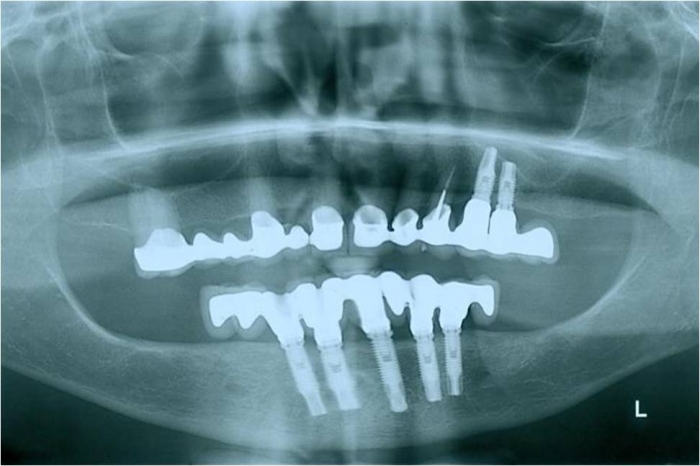

Raio X de controle, realizado em Março de 2012